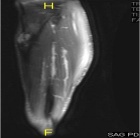

17 year old male c/o left shin pain. He is active in sports. First noted pain while running and with activities. Pain has been intermittent over 9 month period but more constant recently. A palpable lump is present on the left tibia which has not changed in size.